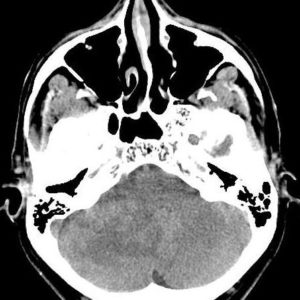

Viêm tai xương chũm